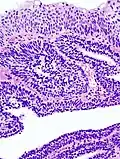

Histopathology representing an inverted papilloma of the urinary bladder that was cystoscopically resected. Hematoxylin and eosion stain. -